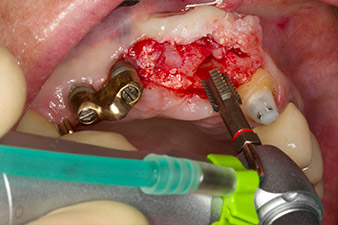

Une fois la cicatrisation primaire obtenue, les tissus mous ont été formés à l'aide du bridge doublé à la base. Deux mois plus tard, la zone a été exposée au moyen d'une incision de la crête alvéolaire légèrement orientée côté palatin (Fig 2). Les dimensions de l'os alvéolaire se sont avérées suffisantes en position 22. Les Figures 2 et 4 illustrent la préparation du lit implantaire, le taraudage et la pose de l'implant à l'aide de l'Implantmed.

Afin de compenser la perte osseuse parodontale et d'obtenir un résultat esthétiquement satisfaisant, la pose de l'implant a été associée à une régénération osseuse guidée (GBR) avec matériau de substitution xénogénique et membrane collagène. (Fig. 5 et 6).